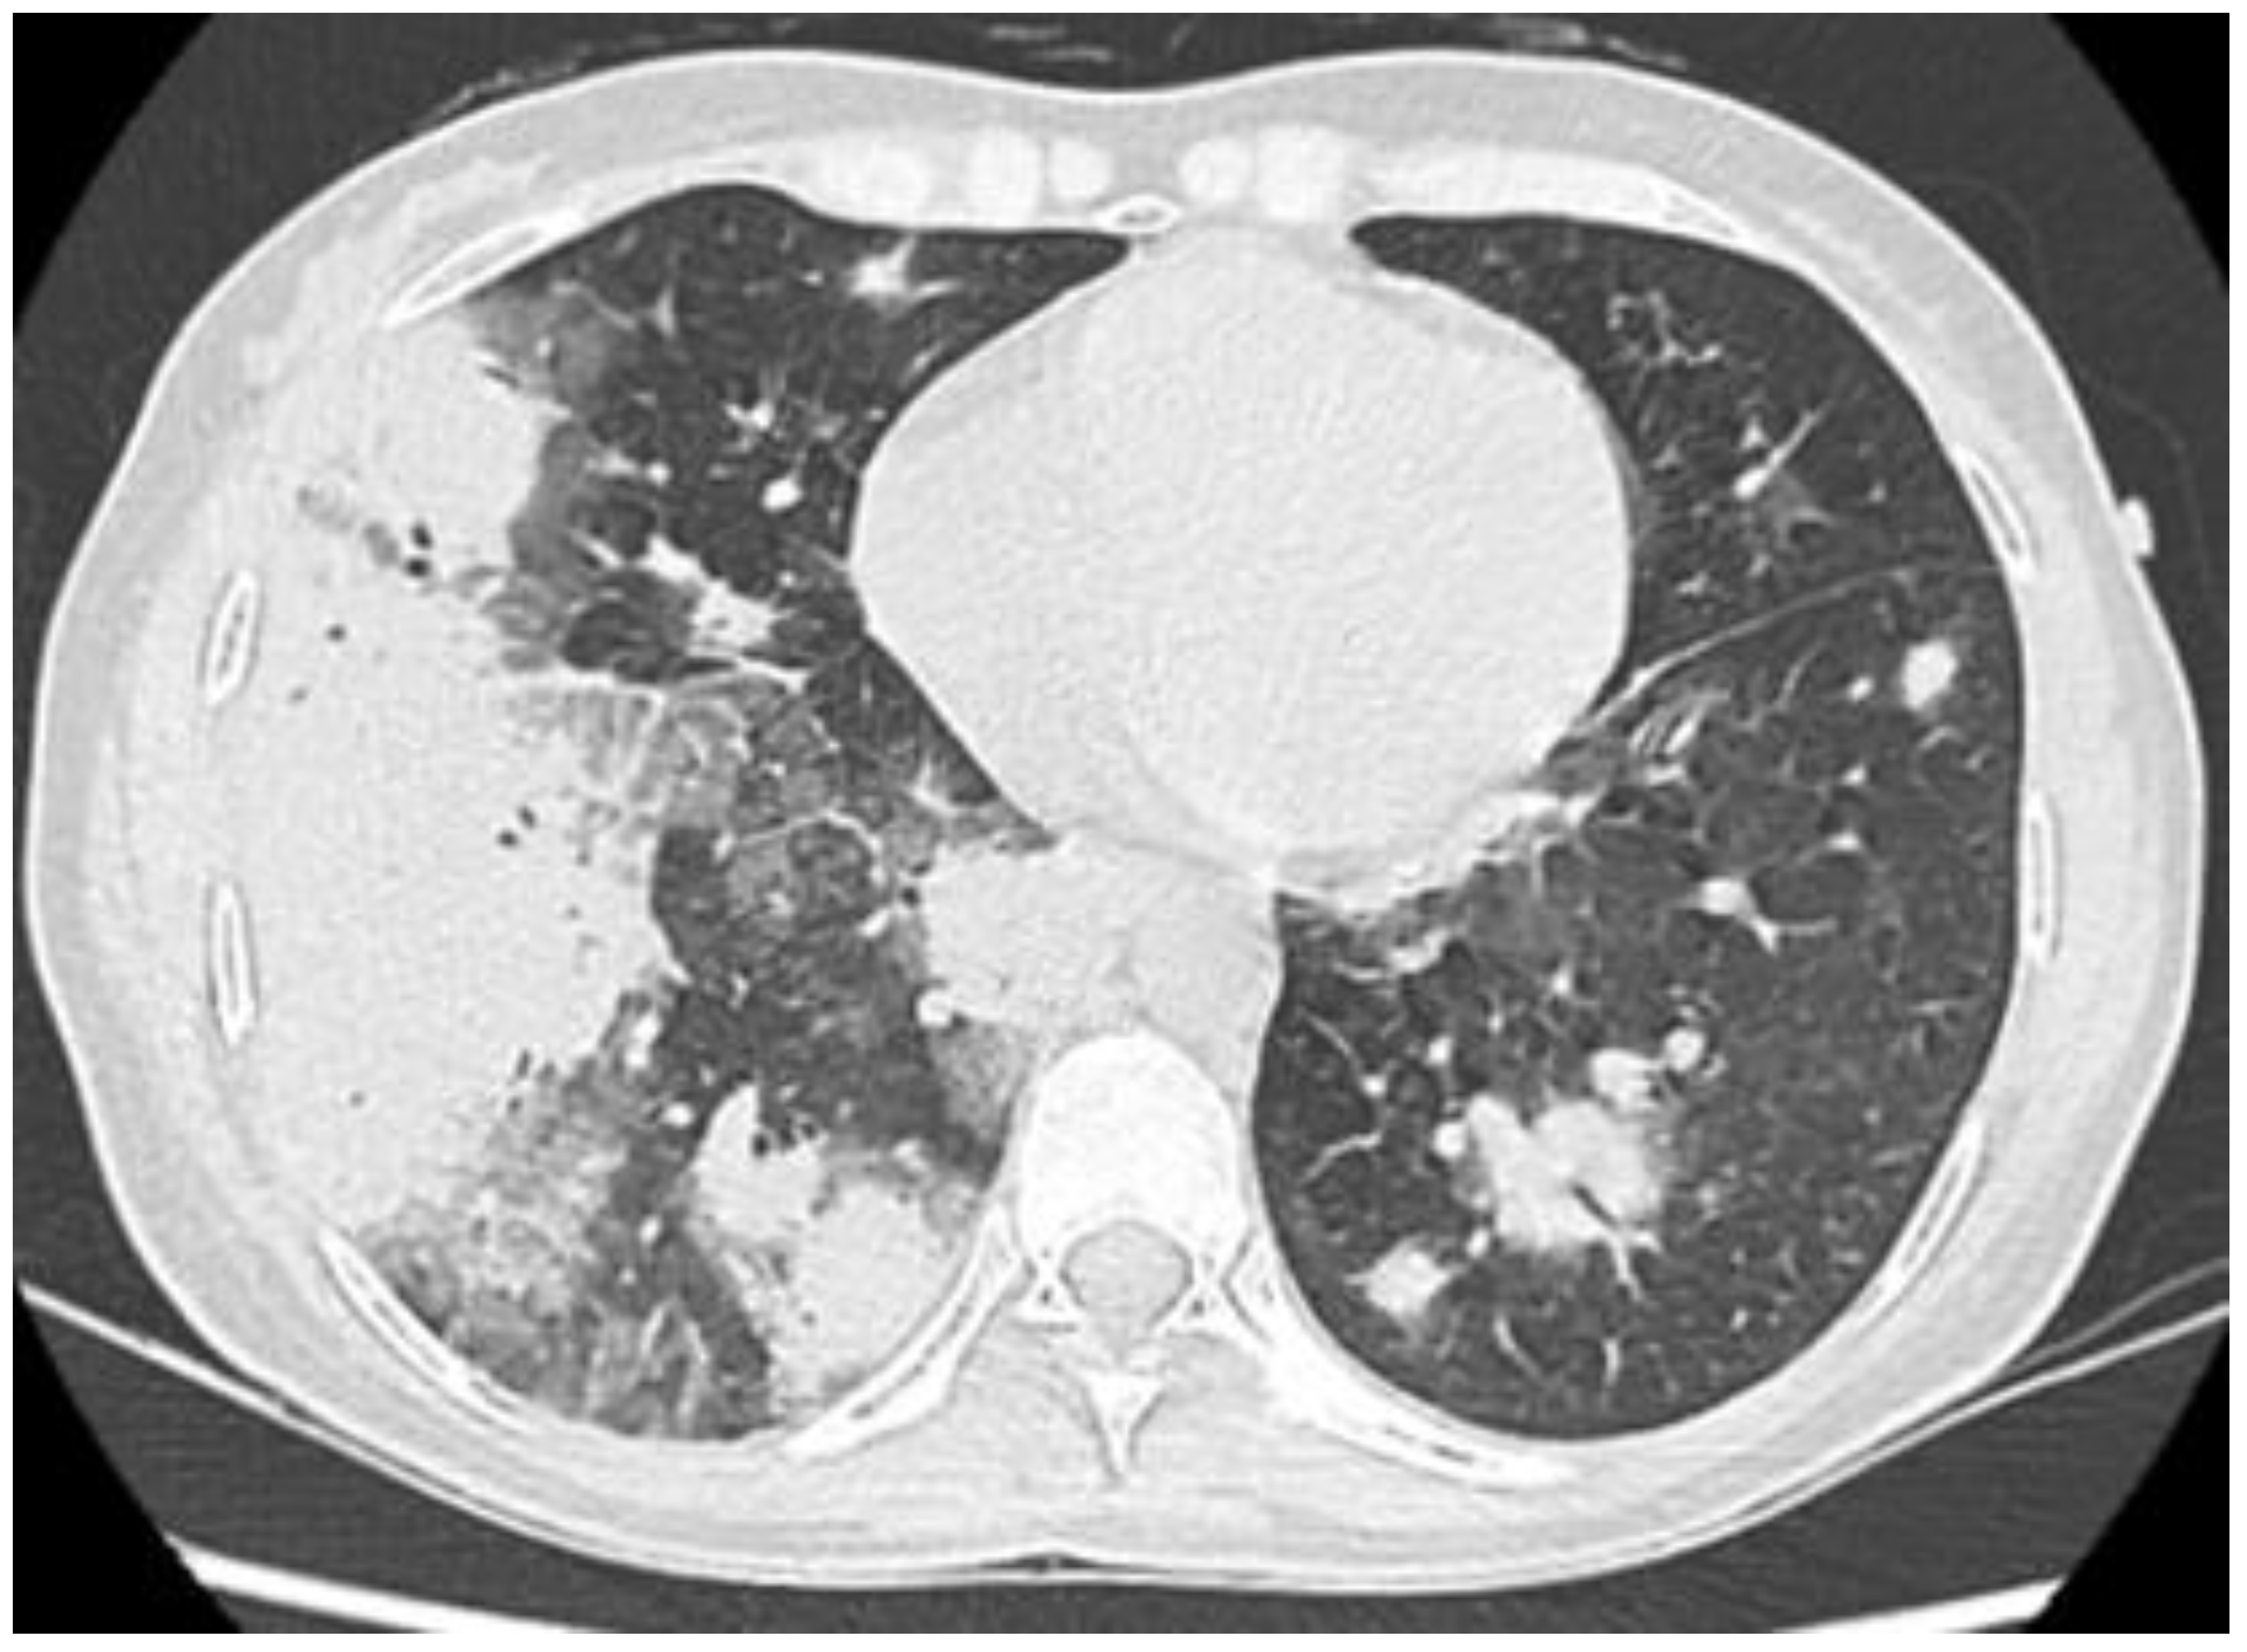

Figure 3.

Extensive bilateral pulmonary consolidations in a 35-year-old female with PBC and OP complicated with acute respiratory failure and rapid improvement after prednisone administration.